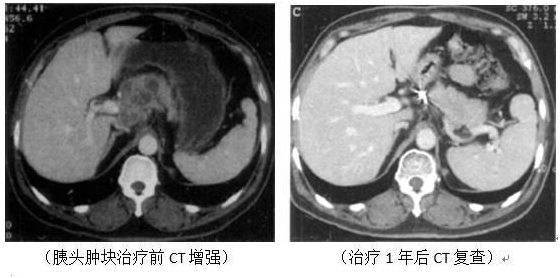

(男性,69岁,右肺鳞癌)